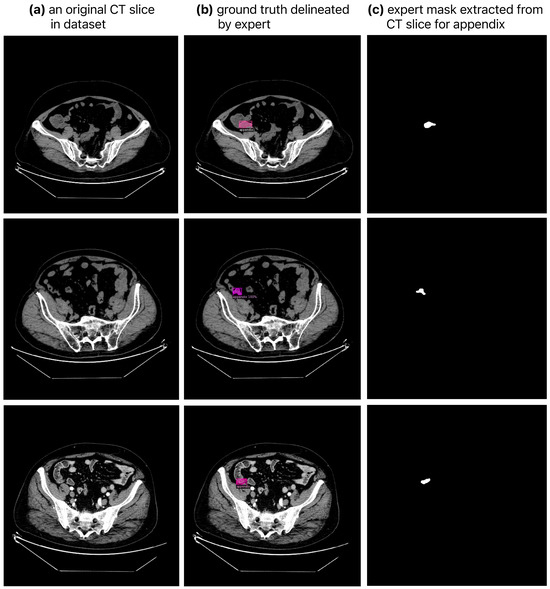

2.1. Dataset